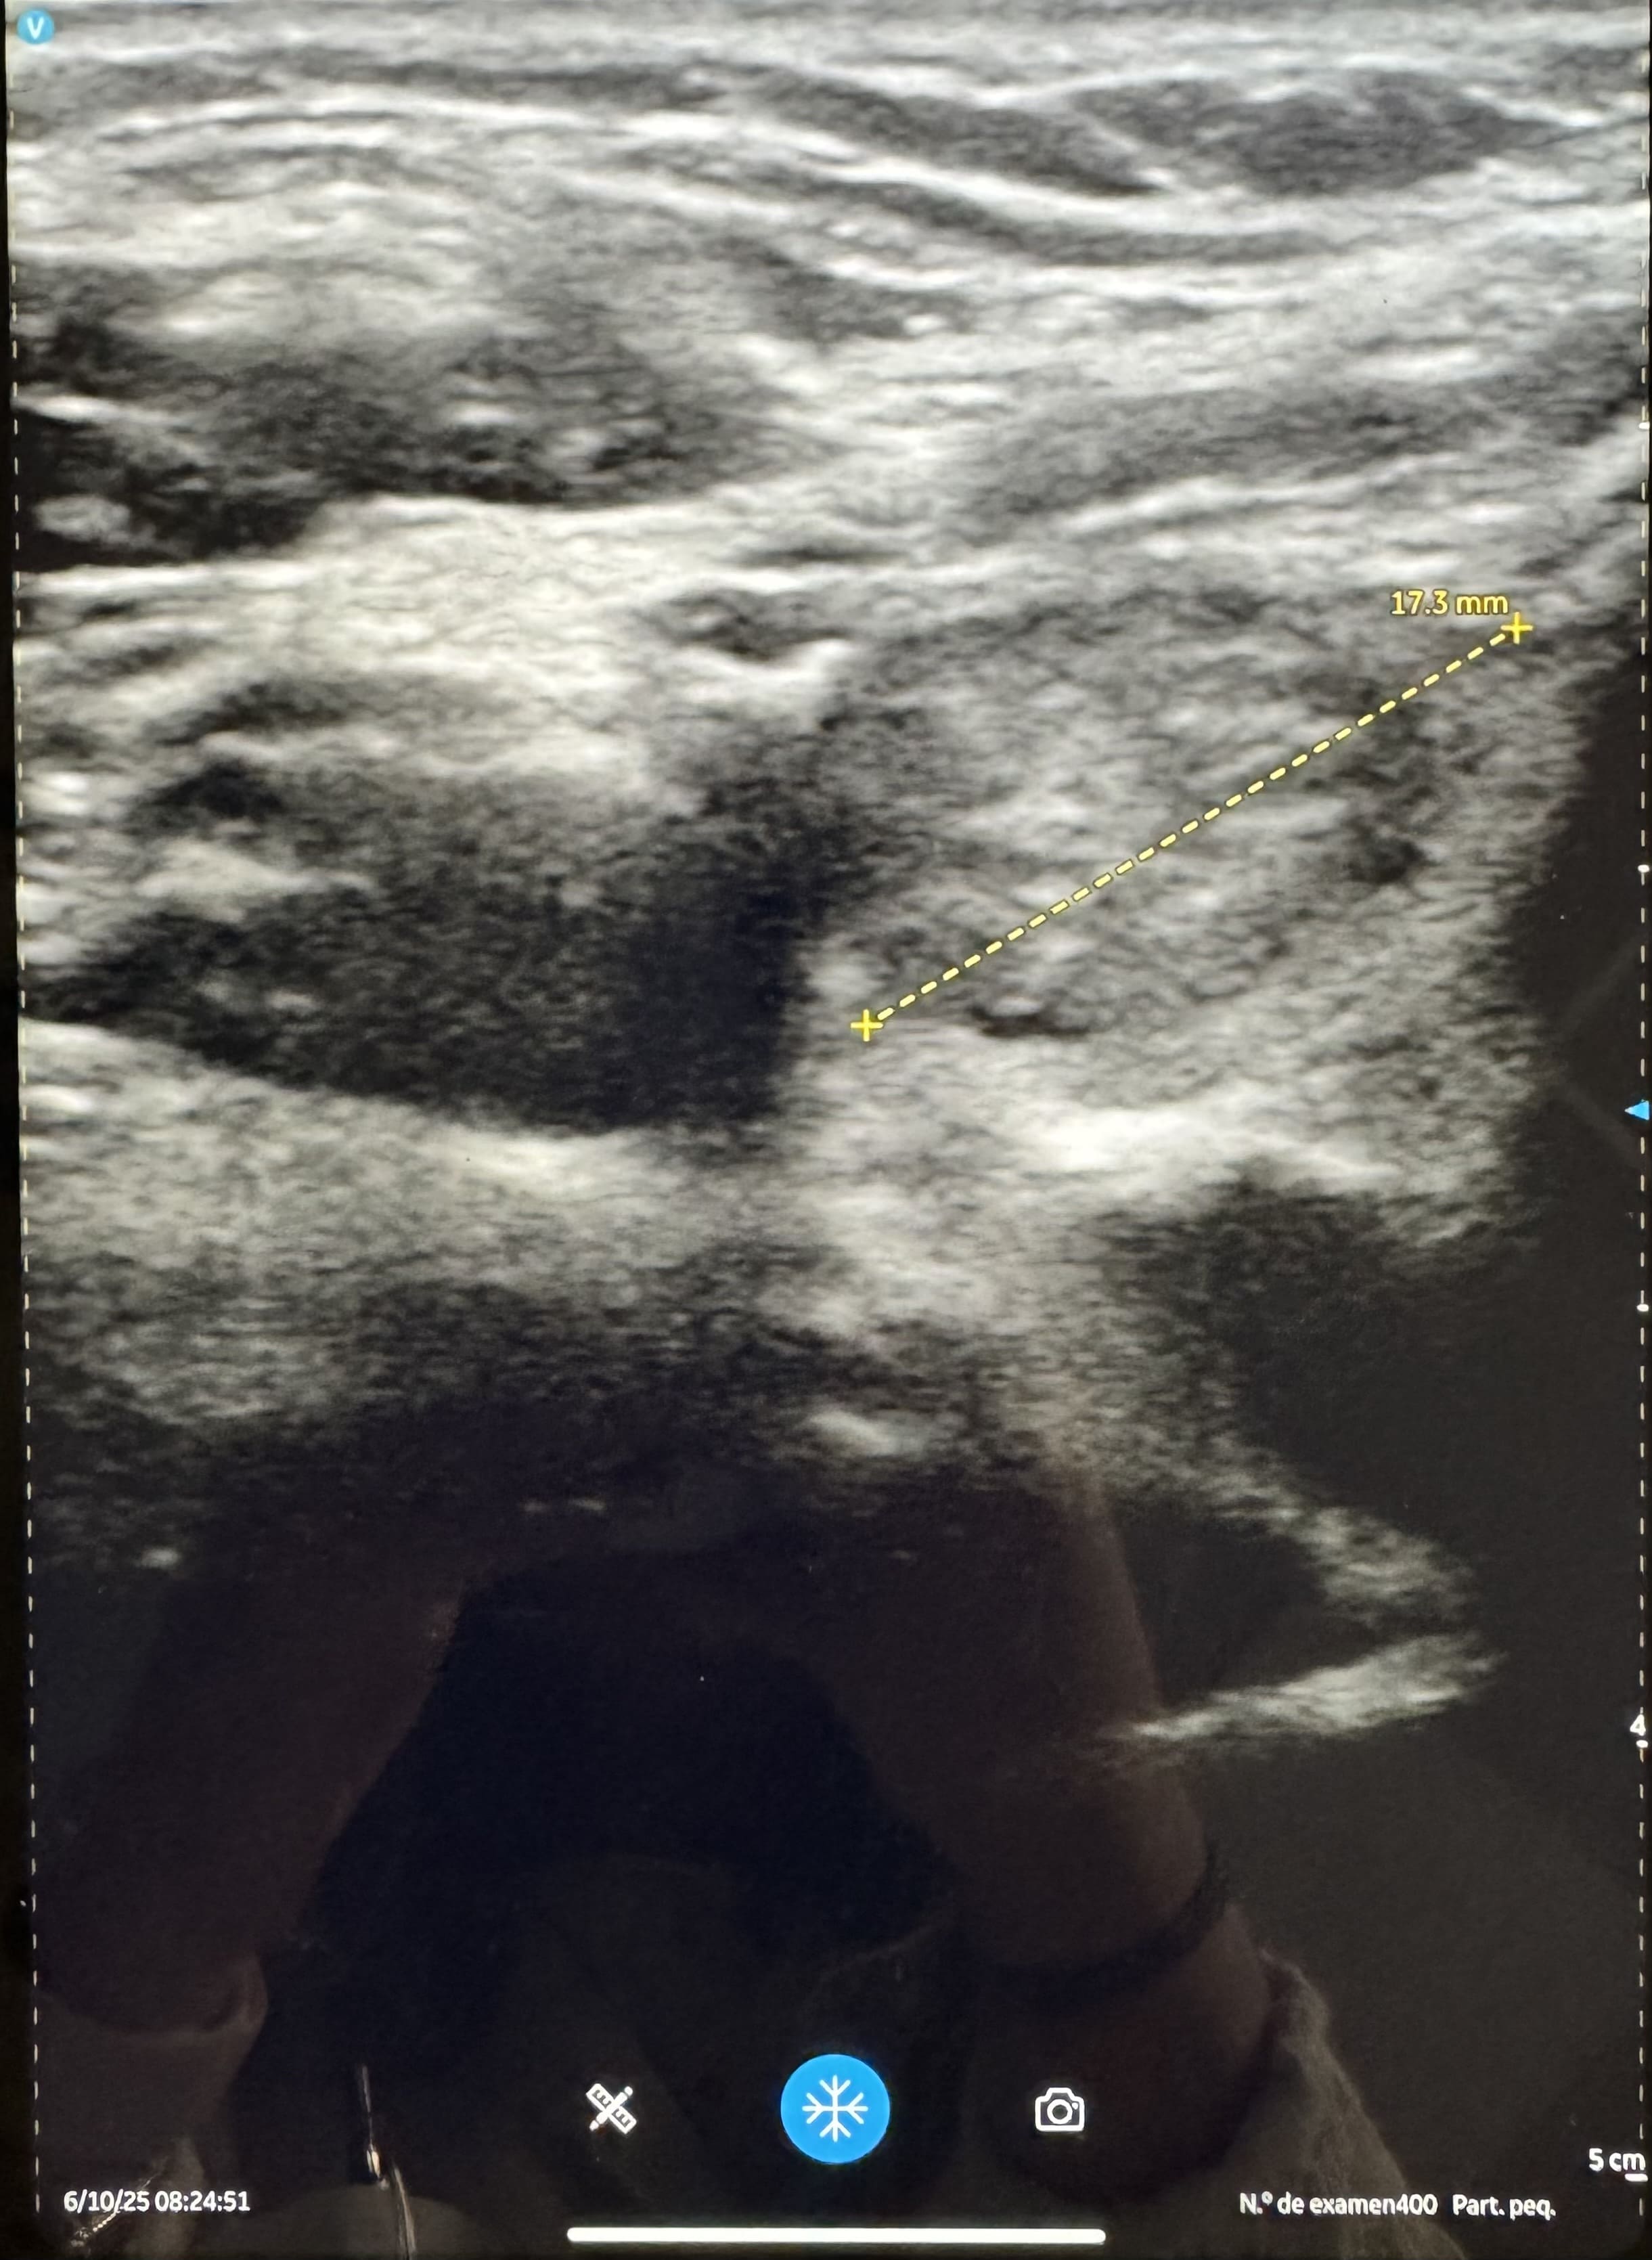

En ecografía realizada en el centro de salud se aprecia tiroides moderadamente aumentado de tamaño, estructura homogénea y con varios nódulos en ambos lóbulos, destacando uno de ellos en lóbulo tiroideo derecho de consistencia mixta e irregular, con algunas calcificaciones en su interior y siendo más ancho de alto 1*7x1.5, apreciándose vascularización periférica.

Tras la realización de la ecografía clínica, se solicita de forma reglada donde describen un tiroides aumentado de tamaño, con nódulos sólidos y homogéneos con escasa vascularización, en probable relación con bocio multinodular. Describen además un nódulo de mayor tamaño en lóbulo derecho de unos 15 mm y con vascularización periférica y componente exofítico, clasificándolo de TIRADS 5, recomendándose así PAAF.